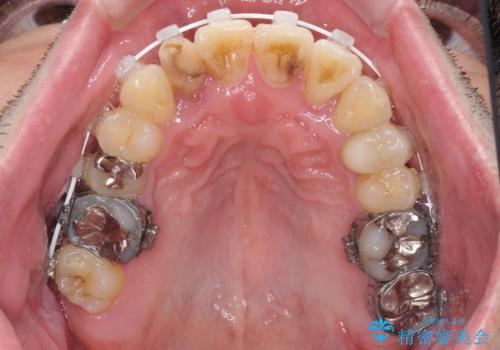

- 奥歯の痛みと前歯のデコボコを気にして来院された患者様です。

左右下顎の大臼歯は、ともに歯根が破折しており、抜歯が必要な状態でした。

咬み合わせは受け口傾向であり、上顎前歯の叢生が顕著であったことから、第1小臼歯抜歯による矯正治療も検討しましたが、下顎大臼歯を左右ともに抜歯するため、非抜歯による矯正治療を行うこととしました。